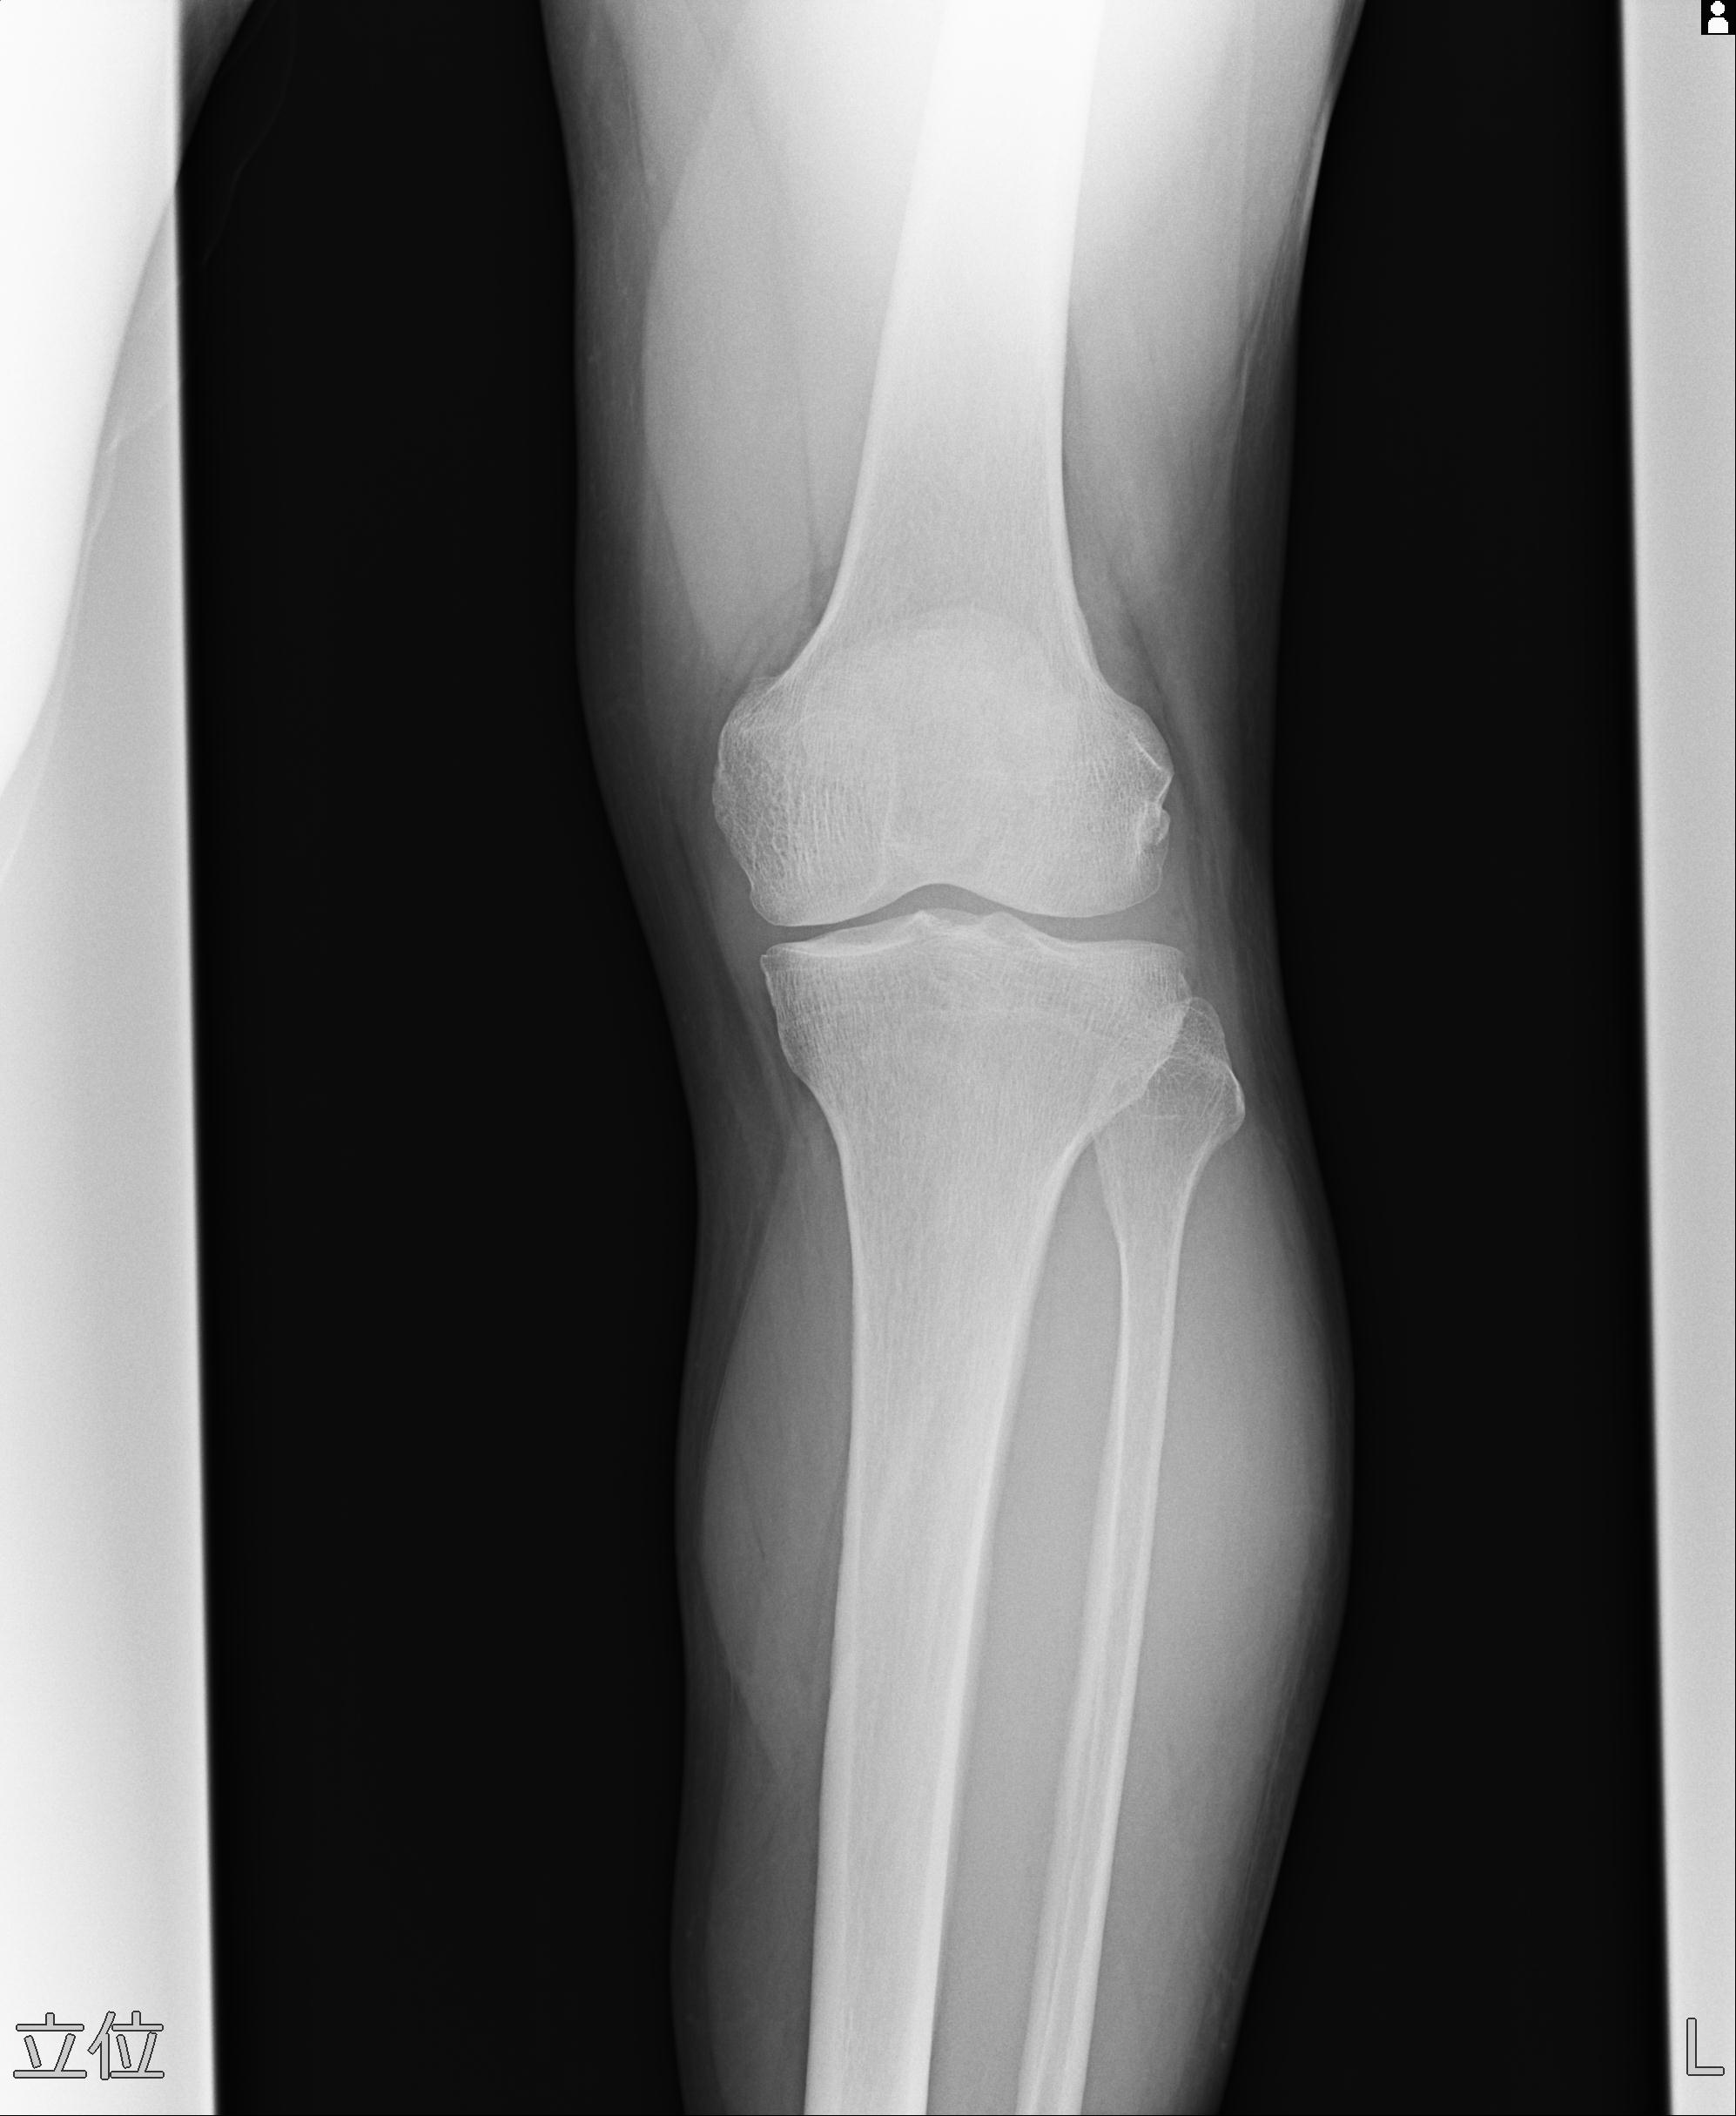

91983 11/16 左膝 2R 11/18 2R 55歳男性 脛骨骨切り術